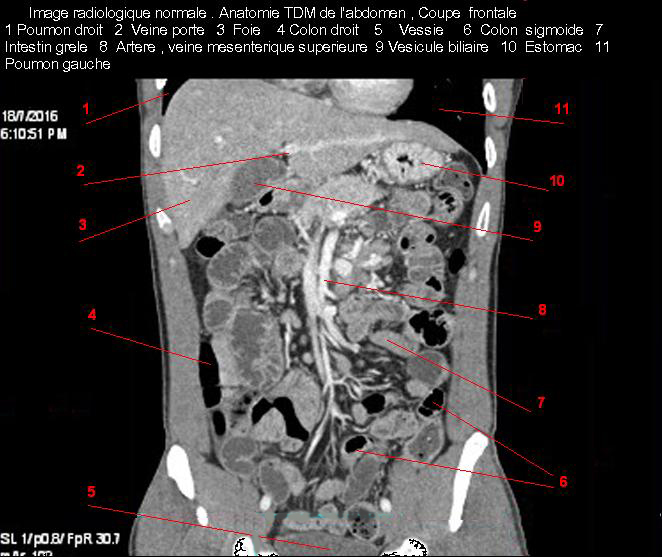

Image radiologique TDM normale de l'abdomen et tube digestif en coupe frontale ( Coronale )  :